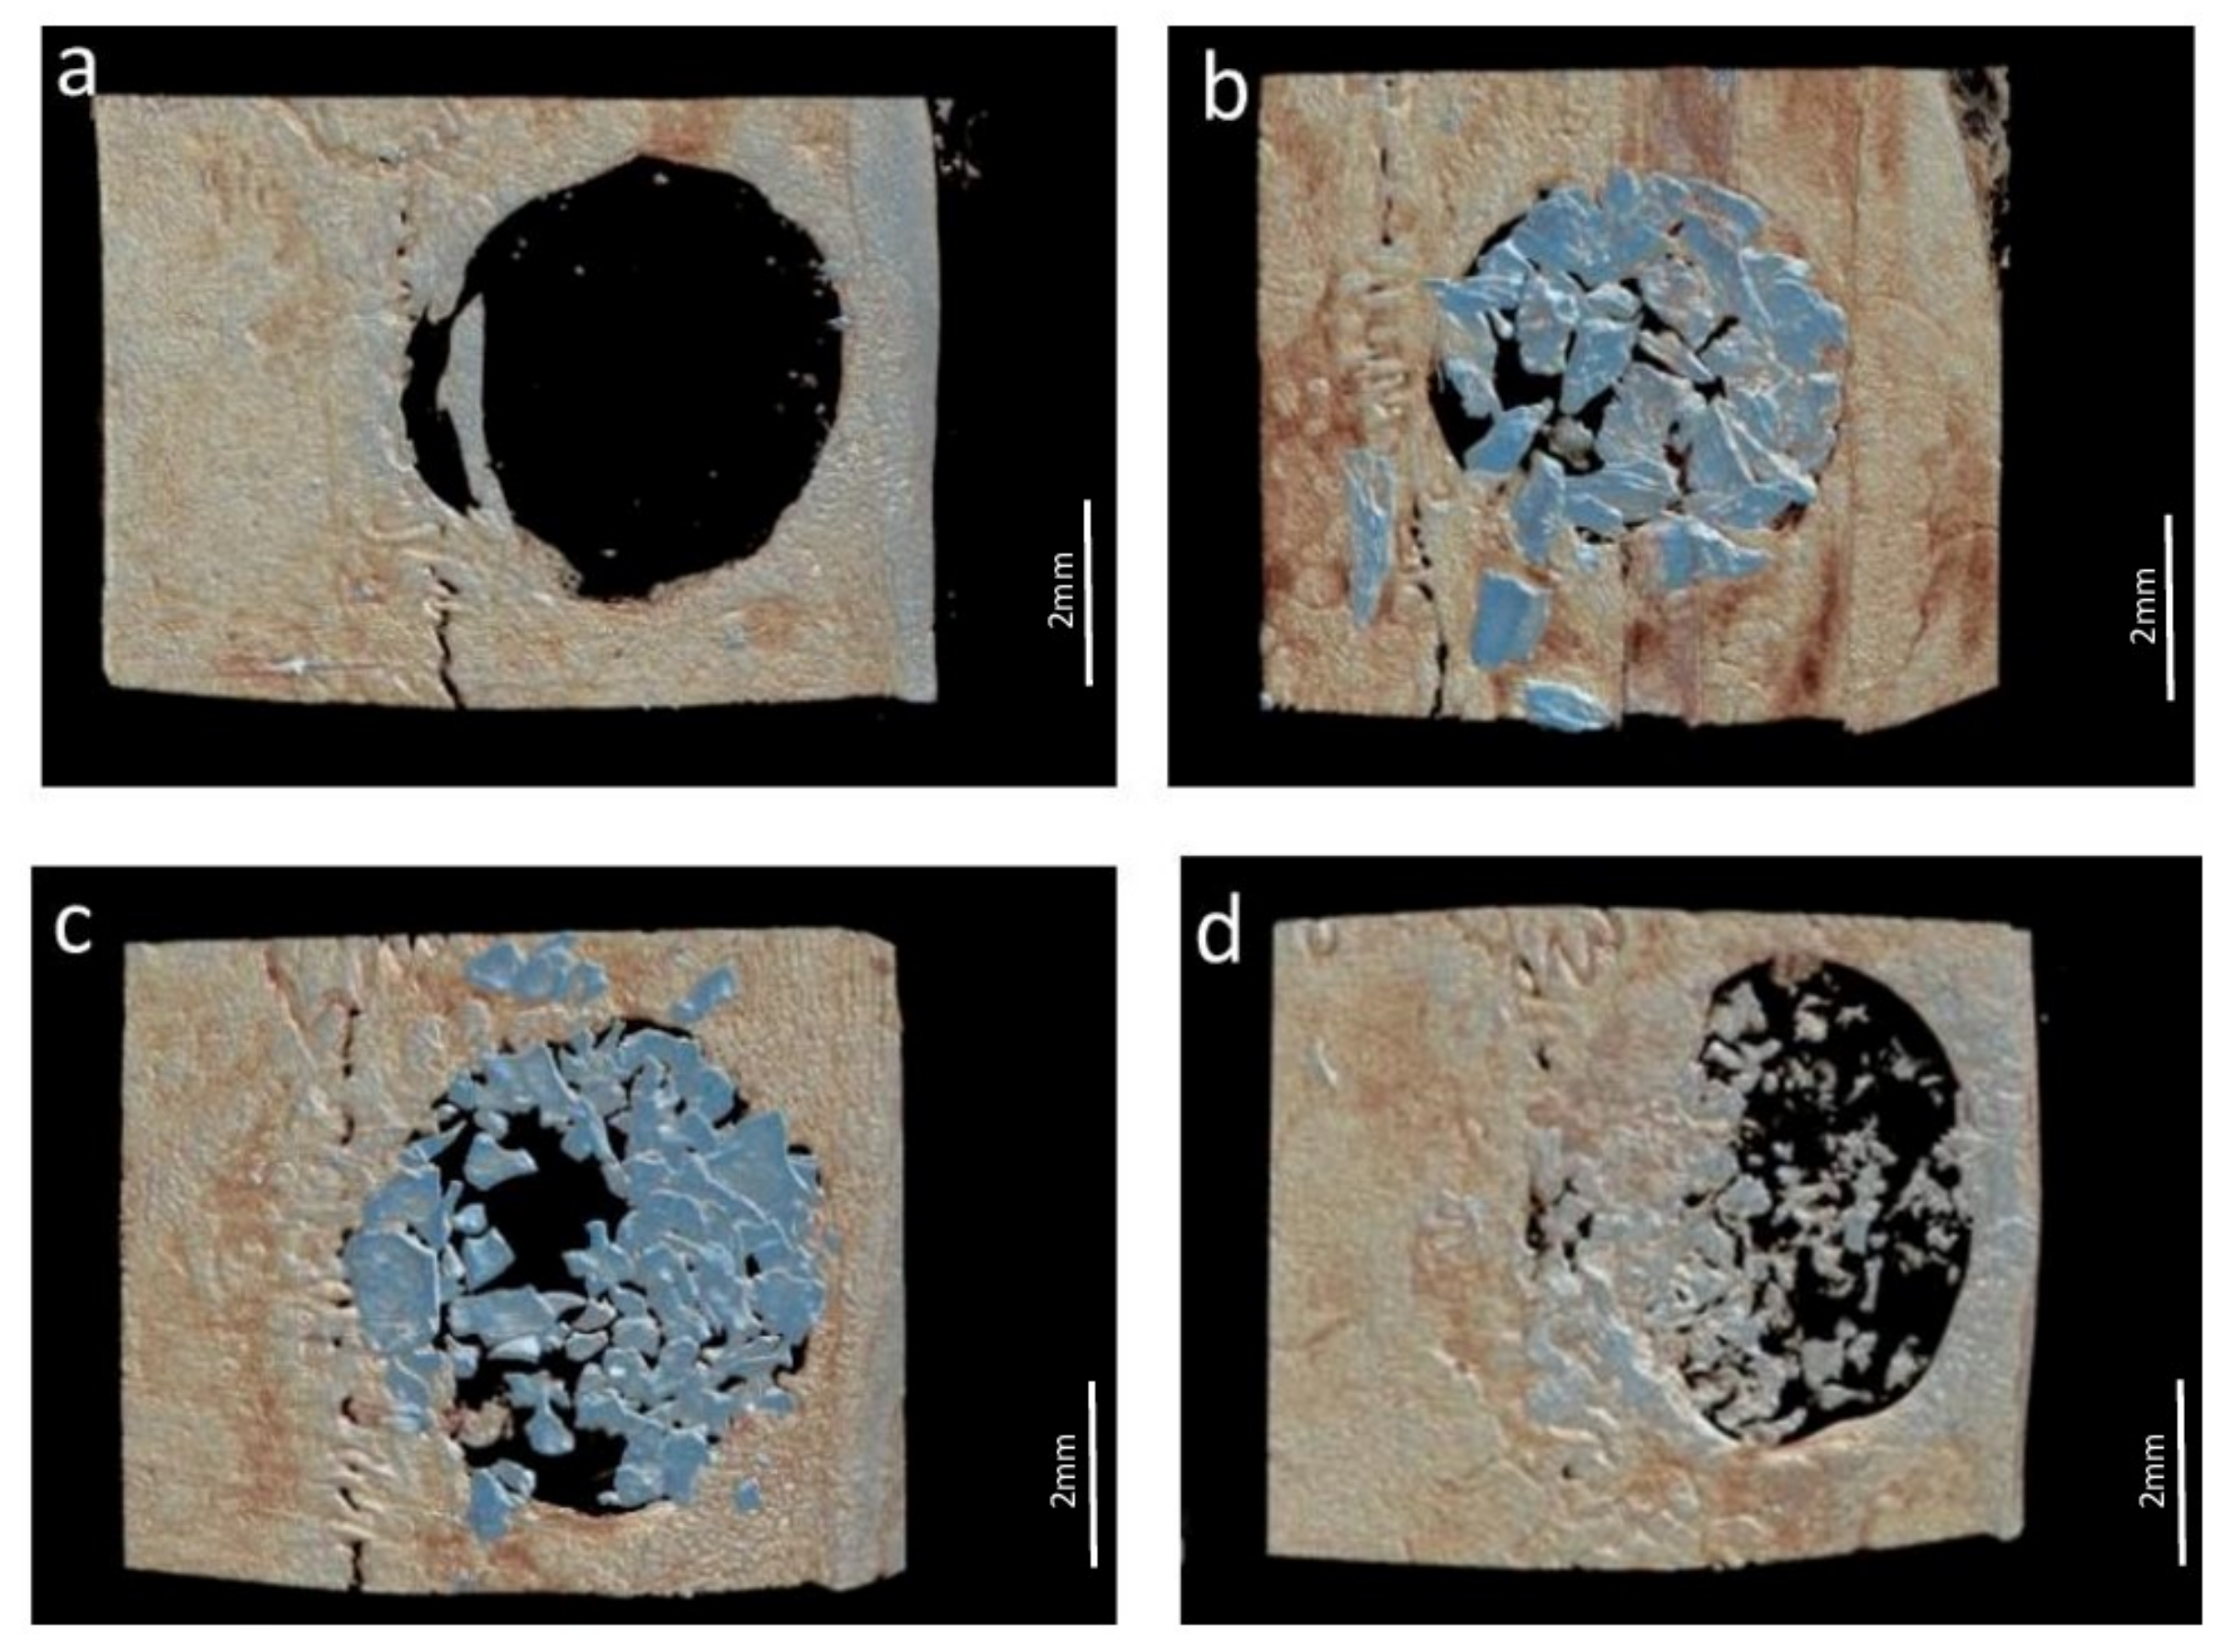

The following parameters were analyzed in each VOI by a calibrated examiner (Y.F.F.) using the CT-Analyser® v.1.13.5.1+ software (Bruker, Kontich, Belgium): Bone surface density (BS/TV), defined as the ratio between the bone surface area and the total volume of the VOI, expressed in 1/mm; bone volume percentage (BV/TV), defined as the ratio between bone volume and the total volume of the VOI, expressed in percentage (%); trabecular thickness (Tb.Th), defined as the average thickness of the trabeculae, expressed in mm; number of trabeculae (Tb.N), defined as the average number of trabeculae per mm, expressed in 1/mm; total Porosity (Po.tot), defined as the percentage of pores per analyzed VOI; bone connectivity (Conn), defined as a measure of the degree to which a structure is multiply connected and the maximum number of connections that can be broken before the structure is separated into two parts. Illustrative 3D reconstructions of each group are shown in Figure 2.

Figure 2.

Micro-CT analysis—three-dimensional reconstructions of the defects. (a) Control Group; (b) Porcine Group; (c) Bio-Oss Group; (d) Bonefill Group.